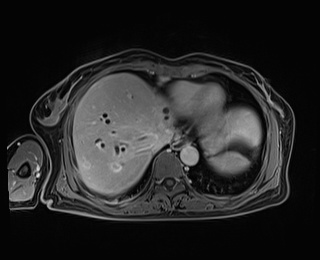

经知情同意后,2021年7月15日在局麻下行PTBD穿刺引流减黄,并于2021年8月2日行肿块活检术,术后病理结果为腺癌,经过减黄、营养支持、护肝等治疗后,患者全身各指标好转后于2021年8月12日开始实施化疗联合免疫治疗进行转化,经过7个月的转化治疗,复查肝胆增强磁共振示:右肝转移灶消失,肝门肿块缩小,同时进一步完善PET-CT,未见肿瘤全身扩散,局部与MRI一致,考虑肿瘤转化降期成功,而此时,患者免疫治疗相关药物不良反应开始出现,表现为皮疹、口腔溃疡等,再次经科内讨论,认为手术条件已经成熟,可以考虑手术治疗,术前完善三维可视化肝脏体积评估,残留左外叶占标准肝体积45.6%,符合指南肝切除预留肝体积指标。

转化治疗前 转化治疗后